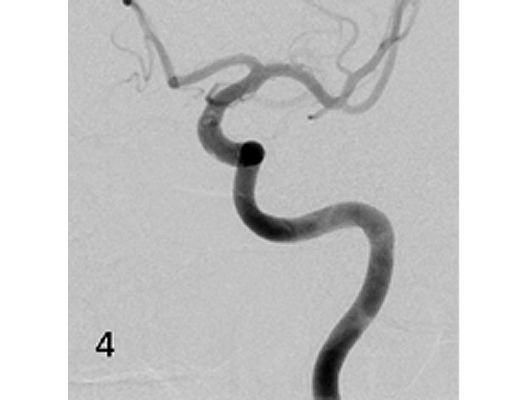

Das Beispiel zeigt die angiographischen Bilder einer Patientin, bei der es zu einer Sehstörung gekommen war. Die Ursache war ein großes Aneurysma der Halsschlagader an der Schädelbasis (Bild 1). Bild 2 zeigt die Lage des Aneurysmas hinter dem Auge. Durch den Druck des Aneurysmas auf den Sehnerv war es zu der Sehstörung gekommen. Die Patientin wurde mit einer speziellen Gefäßprothese versorgt, welche über eine Punktion der Leistenarterie in die Halsschlagader eingesetzt wurde (Bild 3). Bei der Kontrolle nach 6 Monaten zeigte sich ein vollständiger Verschluss des Aneurysmas (Bild 4). Die Sehstörung hatte sich vollständig zurückgebildet.